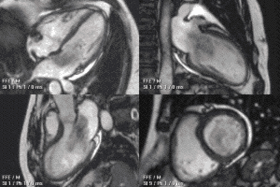

![]() An example of CMR movies in different orientations of a cardiac tumor - in this case, an atrial myxoma.[1] | |

Cardiovascular magnetic resonance imaging (CMR), sometimes known as cardiac MRI, is a medical imaging technology for the non-invasive assessment of the function and structure of the cardiovascular system. It is derived from and based on the same basic principles as magnetic resonance imaging (MRI) but with optimization for use in the cardiovascular system. These optimizations are principally in the use of ECG gating and rapid imaging techniques or sequences. By combining a variety of such techniques into protocols, key functional and morphological features of the cardiovascular system can be assessed.